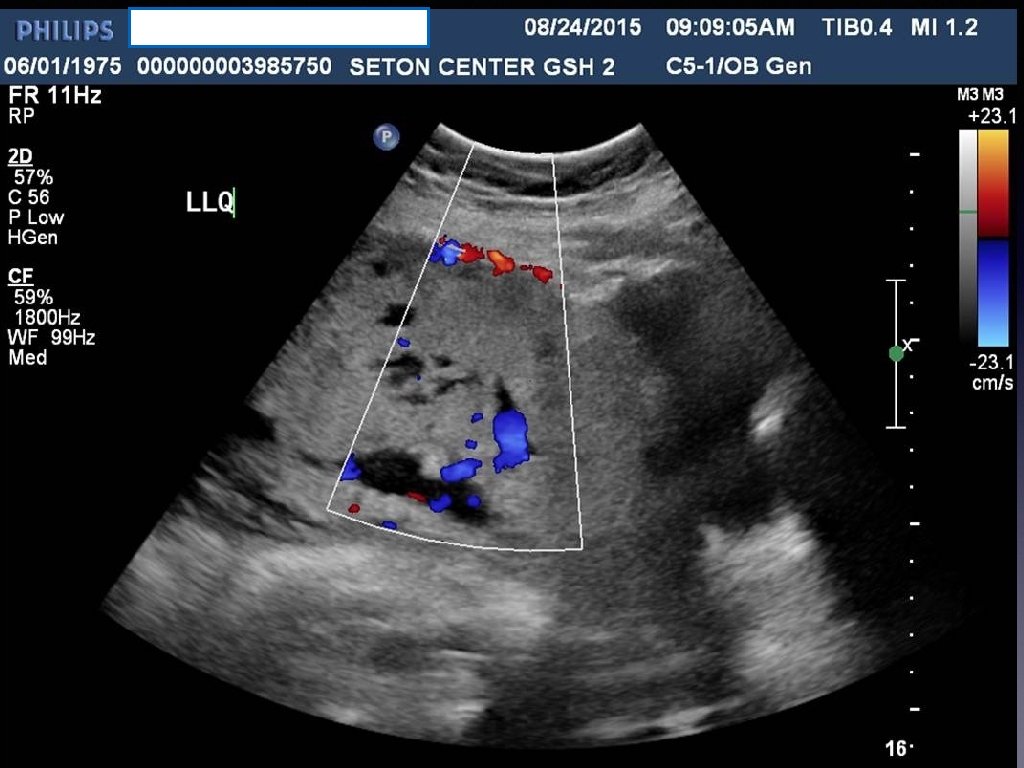

Prenatal Diagnosis • When the diagnosis is made it is usually made by ultrasound in the second or third trimester. • Sonographic findings suggestive are • • loss of normal hypoechoic retroplacental zone • multiple vascular lacunae (irregular vascular spaces) within the placenta “swiss cheese” appearance • blood vessels or placental tissue bridging the uterine-placental margin, myometrialbladder interface, or crossing uterine serosa • retroplacental myometrial thickness < 1 mm • numerous coherent vessels visualized with 3 -D color/power Doppler in a basal view. If sonographic findings are inconclusive or a placenta percreta is suspected, MRI may be useful.

Ultrasound Findings Suggesting Morbidly Adherent Placenta • Third trimester • Loss of normal hypoechoic retroplacental zone • Presence of multiple vascular lacunae within placenta (Swiss-cheese appearance) • Abnormalities of uterine serosa-bladder interface (intertuption of line, thickening of line, irregularity of line, and increased vascularity • Extension of villi into myometrium, series, or bladder • Retro-placental myometrial thickness of< 1 mm • Turbulent blood flow through lacunae on Doppler ultrasonography • Increased subplacental vascularity • Vessels bridging form placenta to uterine margin • Gaps in myometrial blood flow